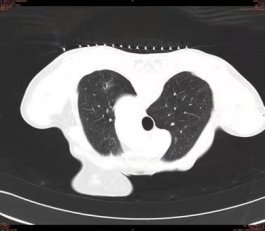

患者,男,70岁,体检时无意中发现左肺上叶磨玻璃密度灶,病灶范围约3CM左右,恶性表现明显。经多学科会诊,建议手术切除。

17日上午,影像科副主任马亮为患者进行术前定位。先行胸部CT扫描,固定患者体位,确定进针点,测量进针深度及角度,局麻后用肺结节定位针缓缓刺入肺组织中,到达病灶下界边缘后留置,CT再次扫描证实针尖位置与术前计划一致,拔出针芯,释放定位钩,推送定位线至胸壁内。术毕即刻送患者到手术室成功进行了胸腔镜下切除术。